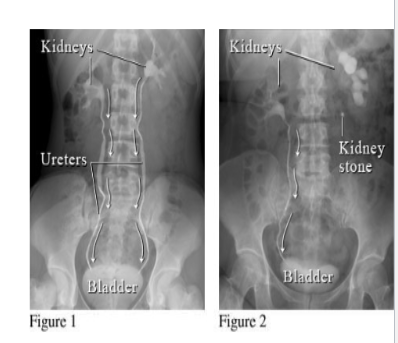

Where are normal spots in which renal calculi (stones) may get impacted

ureteropelvic junction: where the renal pelvis joins the ureter.

as the ureter crosses the pelvic brim: at the bifurcation of the common iliac artery.

ureterovesical junction: where the ureter pierces Obliquely through the wall of the urinary bladder.

Describe Urinary Tract Stones (renal calculi )

Etiology

Patient presentation

Treatment?

Etiology:

More common in men ( 20-60 years) and associated with sedentary lifestyle.

Patient Presentation:

patient complains of severe intermittent pain ( ureteric colic) which may be felt from loin to groin , proximal anterior aspect of thigh or external genitalia . (T11- L2).

May also have blood in the urine ( hematuria )

Treatment:

Lithotripsy sends a shock wave that breaks the stone into

fragments which then pass in the urine.